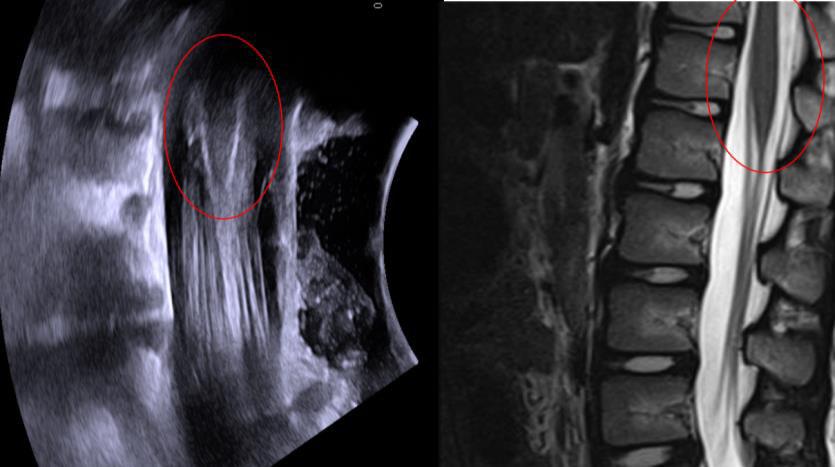

Functional mobility level and baseline gait quality are both important factors to predict gait outcomes after SDR. If candidates are well selected, SDR can be a successful intervention to improve gait both in children with spastic diplegia.